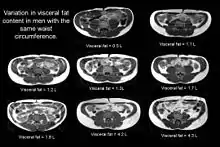

To classify an individual as TOFI, it is essential to measure their internal fat content. This is done by using magnetic resonance Imaging (MRI) or CT scanning. The parameters of the MRI scanner are manipulated to show fat as bright (white) and lean tissue as dark.

Indirect methods such as waist circumference are not suitable as individuals with an identical waist circumference can have vastly different levels of internal fat.

The figure clearly shows that despite having an identical waist circumference (in this example all men had a waist of 84 cm), there is considerable variation in the amount of visceral fat (volumes shown on the image in litres) present.